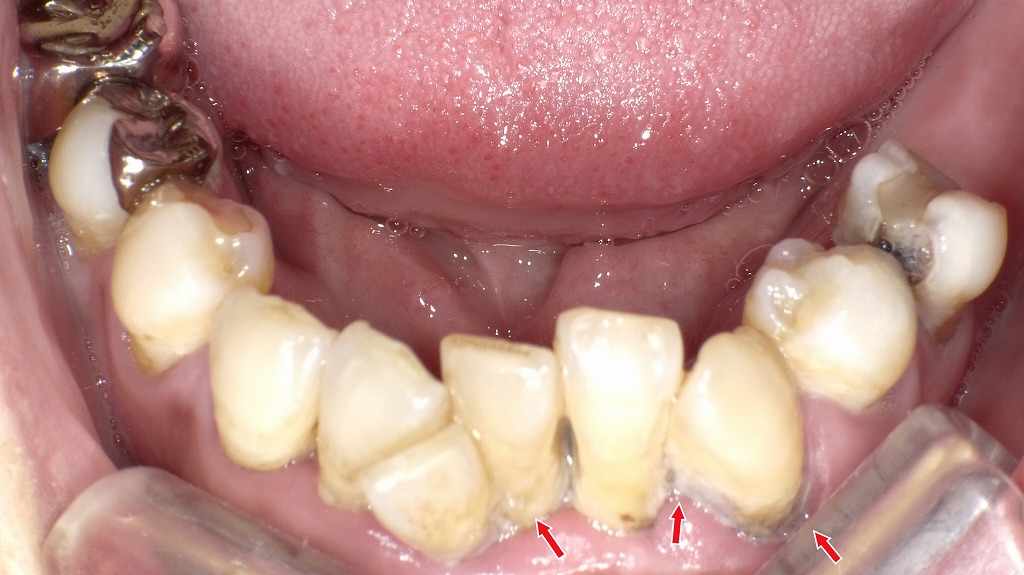

下顎前歯には大量の歯垢と硬く固着した歯石(赤矢印部)が認められ、歯周病が進行した状態です。歯周病によって増殖した細菌は、唾液とともに口腔内に常に存在し、嚥下機能が低下した高齢者では、これらの細菌を誤って気管に吸い込むことで誤嚥性肺炎のリスクが高まります。清潔な口腔環境を保つことは、全身の感染予防にも直結する重要なケアです。